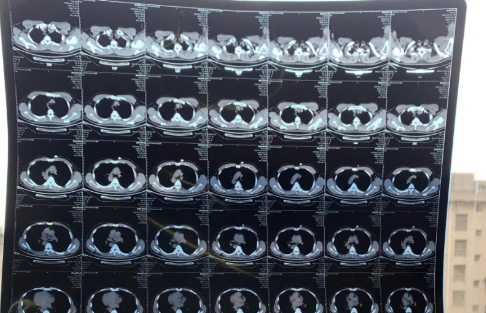

84岁老人肺全白有救吗

一般来说,84岁老人肺全白的话会比较难治,但不存在有没有救的说法。80岁老人肺部白,出现肺部感染的情况是比较难治好的,一般只能针对性进行治疗以控制病情。年高体弱治疗不及时者有可能会进一步发展为心、肺等等多器官的衰竭,甚至可能会出现昏迷、休克、死亡的严重后果。

新冠肺部白化能恢复吗

新冠肺部白化能不能恢复、能不能痊愈,要看症状的严重程度以及自身免疫力。如果是自身免疫力较强,且症状比较轻的,而又是得到及时治疗和有遵医嘱积极治疗的,这种情况下,新冠白肺是有可能会痊愈的,但也有可能会留下肺部纤维化的后遗症。